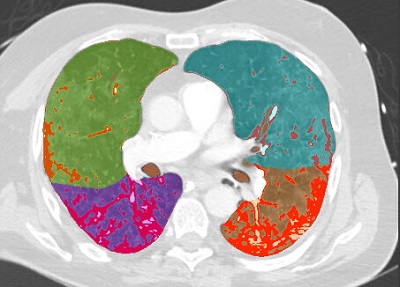

COPD

Quantify diffuse lung disease

CT COPD helps visualize and quantify the destructive process of diffuse lung disease (e.g. emphysema). The application provides a guided workflow for airway analysis, reviewing and measuring airway lumen, and assessing air trapped.

• Automatic lung and lobes segmentation,

• Automatic airway extraction, airway tree segmentation and navigation path extraction, enabling the measurement of airway parameters such as lumen diameter and wall cross section.